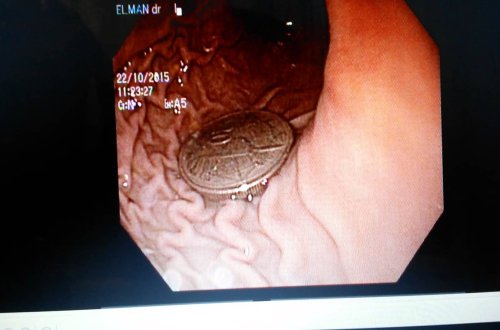

4 yaşlı uşağın mədəsindən `qəpik` çıxdı

həkim

cismin

nəticəsində

xaric

cərrahı

cəmil

İbrahim

Əfəndiyev

qastroenteroloq

ümumi

qərar

endoskopik

yolla

edilməsinə

kamilli

verilib

rasim

sağlam

uşaq

vəziyyətdə